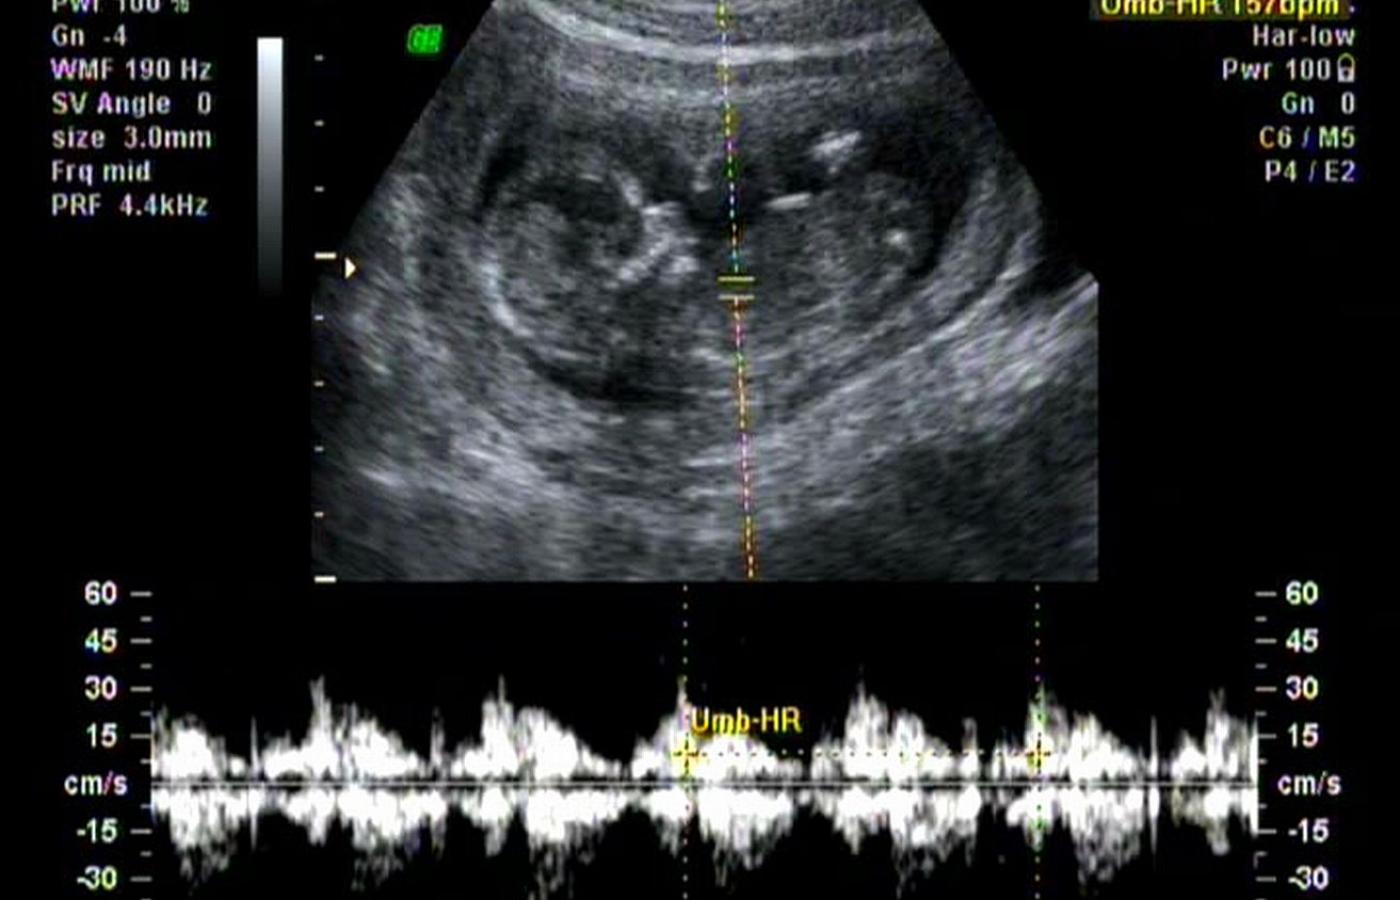

Skan badania ultrasonograficznego serca 13-tygodniowego płodu.MArcel Barteler/Wikipedia Skan badania ultrasonograficznego serca 13-tygodniowego płodu.